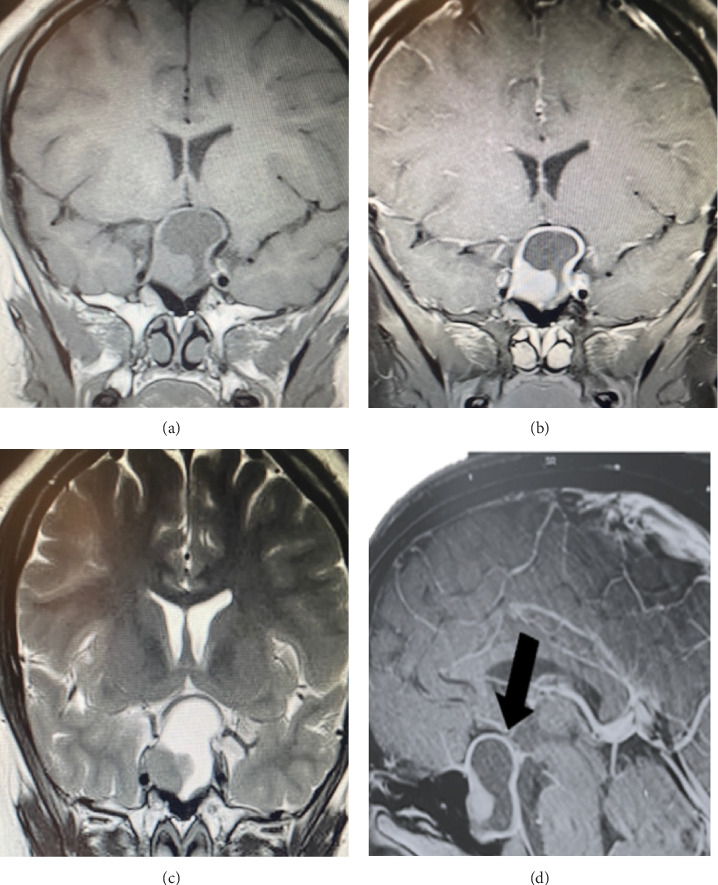

Prolactinoma is the most common pituitary tumor, with clinical presentations varying according to sex, age of onset, tumor size, and prolactin (PRL) levels. These tumors are rare in the pediatric and adolescent populations. Hyperprolactinemia leads to hypogonadotropic hypogonadism, resulting in reproductive, metabolic, sexual, and skeletal consequences that can affect puberty development. Here, we present the case of a 23-year-old male patient diagnosed with arrested puberty secondary to a macroprolactinoma. The clinical presentation, diagnostic approach, therapeutic management, and a literature review are discussed.